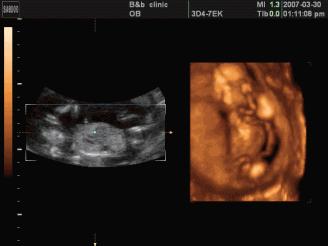

是立体动态显示的彩色多普勒超声诊断仪,可以进行胎儿头面部立体成像,可显示眼、鼻、口、下颌等态势,协助医生直接对胎儿先天畸形进行诊断,价格比普通彩超价格贵。

四维彩超能够对胎儿进行动态、立体超声检查,显示胎儿的面部、各器官的发育情况,甚至胎儿在母体里的态势也可以视察到;对胎儿畸形,如唇裂、腭裂、骨骼发育异常等能早期诊断。另外还能制作成光盘,让宝宝拥有最完整的0岁相册,留下永久的记忆。